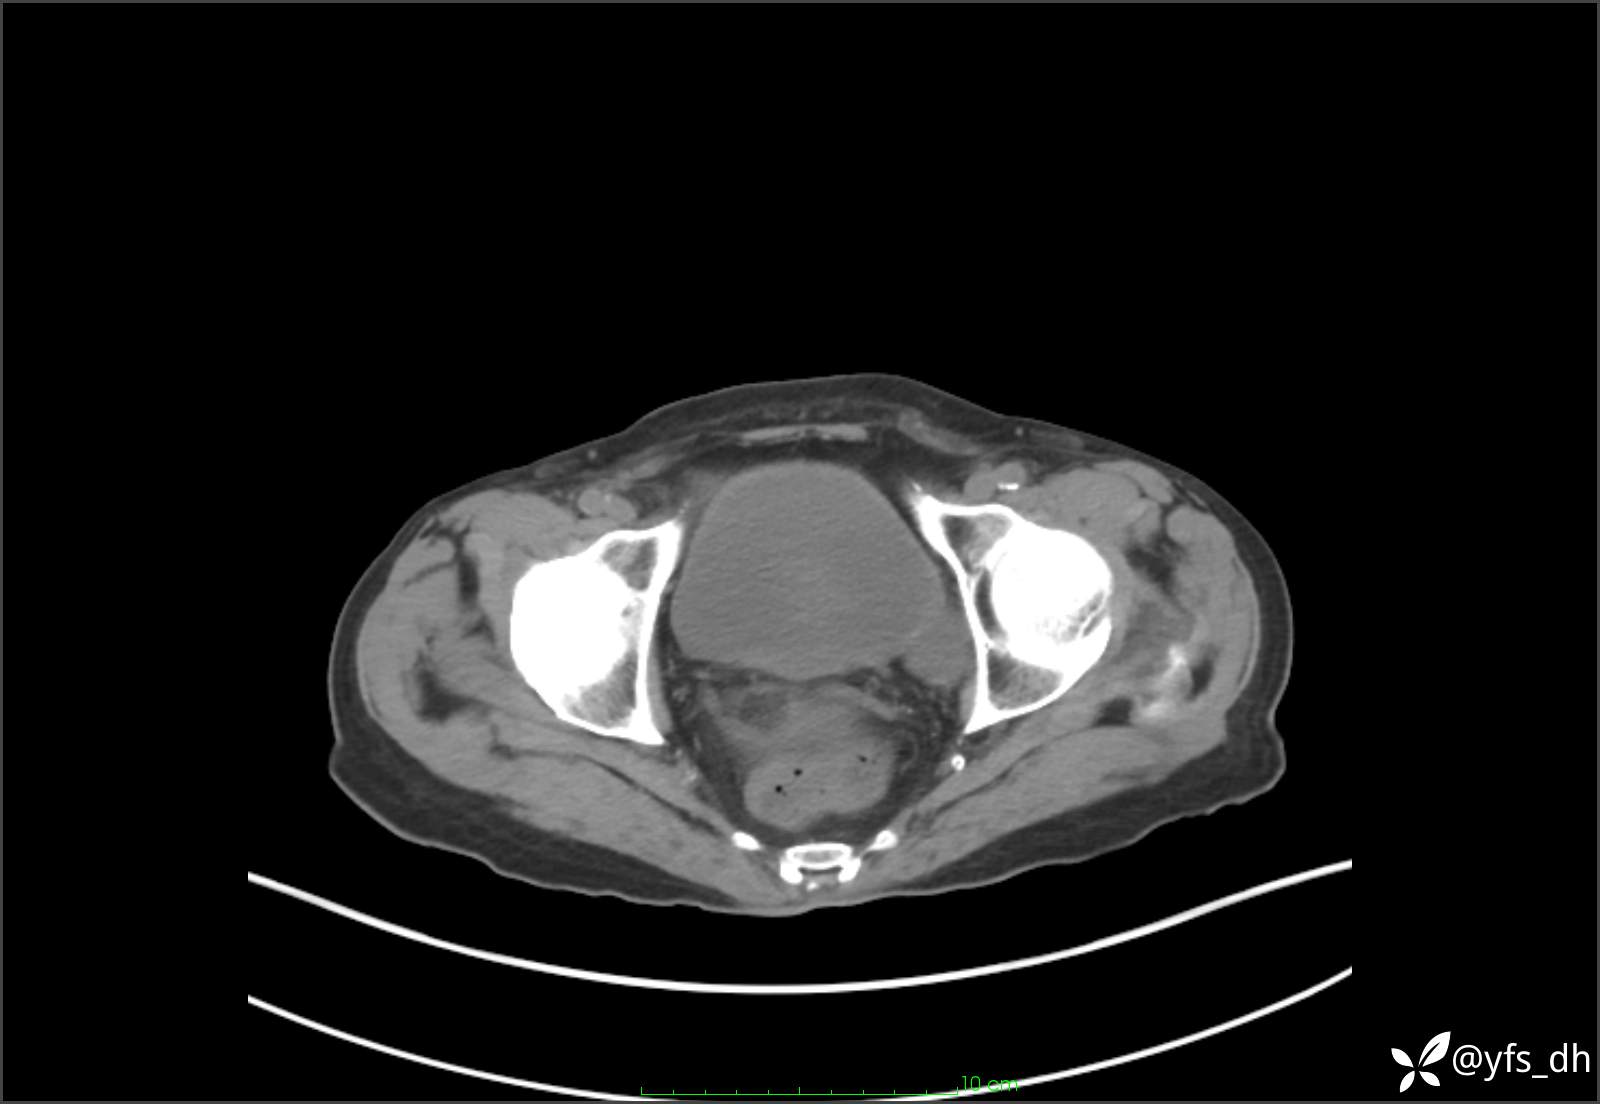

1.简要病史:患者4天前突发上腹部疼痛不适,但可以忍受。3小时前饭后突然加重,不能忍受后就诊。

2.简要手术记录:术中见腹盆腔大量肠液及粪便,乙状结肠中下段见一约3cm的破口。